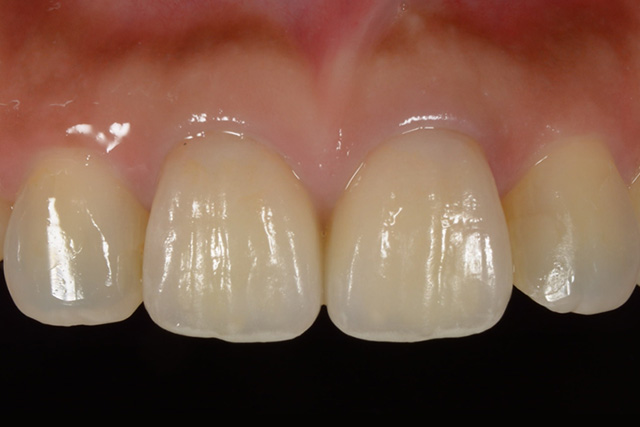

審美症例